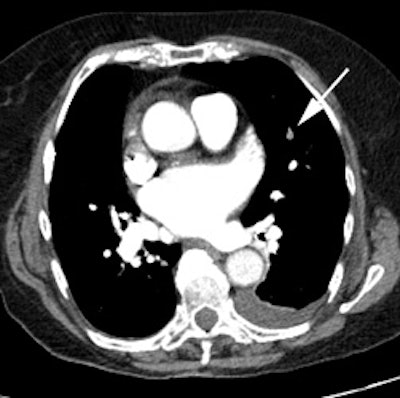

Intermediate probability scan for pulmonary embolism: The patient shown below had a single large segmental perfusion defect in the superior ligular segment of the left upper lobe. Further evaluation was recommended to exclude a pulmonary embolism. A CT PE study confirmed the presence of a PE in this segment. No other emboli were identified. |